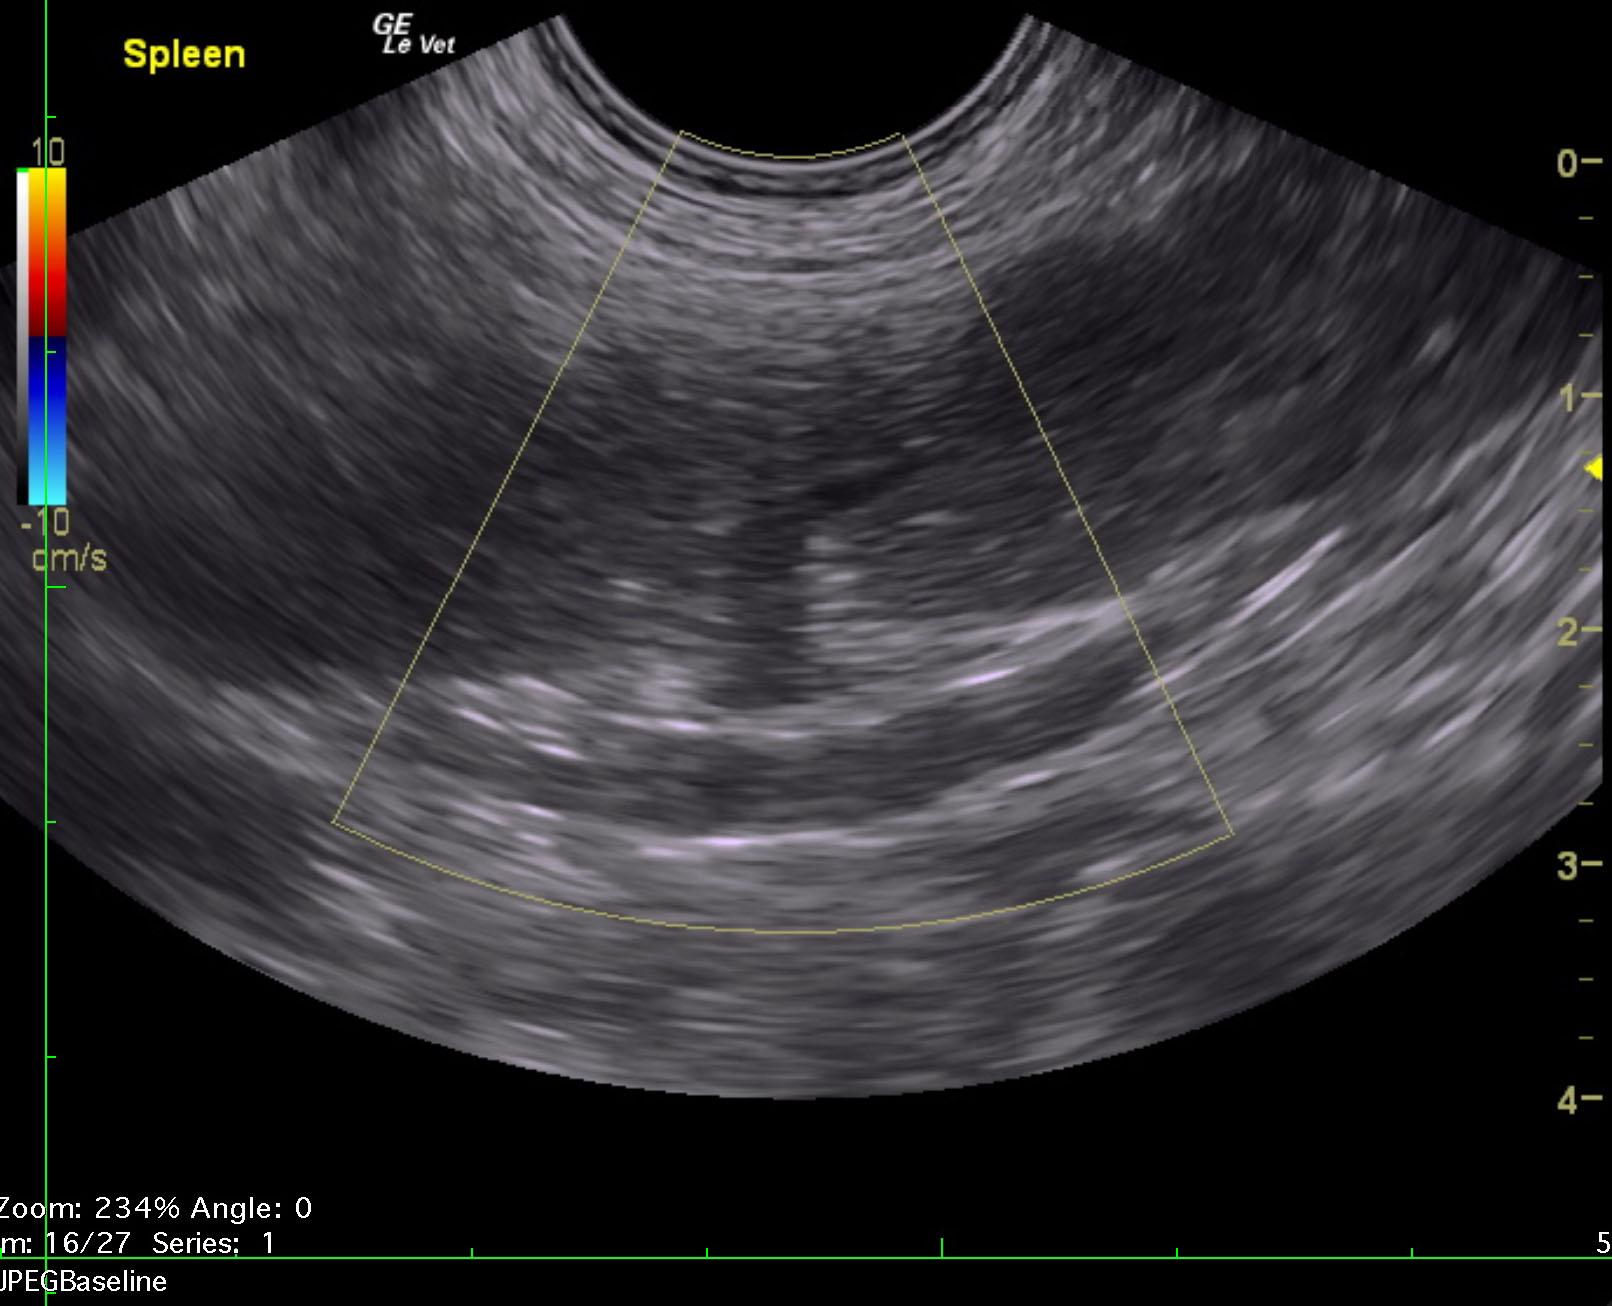

A 10-year-old intact male Komodor with a history of bleeding from the penis was presented recumbent and dyspneic. Abnormalities on CBC and serum biochemistry were leukocytosis, band neutrophilia, monocytosis, azotemia, mild hyperglobulinemia, mildly elevated liver enzyme activity and hyperbilirubinemia.